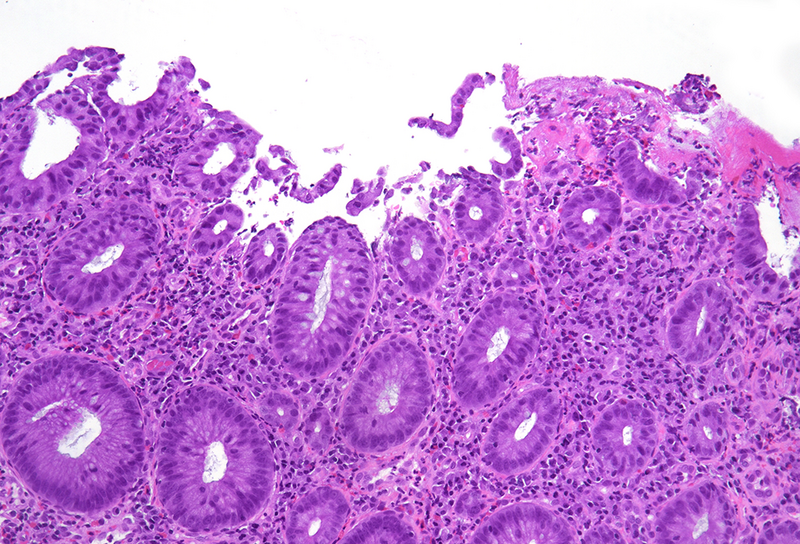

Histology revealed colonic mucosa with preserved architecture. Multiple erosions, crypts with degenerative features and increase of the inflammatory cell infiltrate in the lamina propria, especially granulocytes, were observed (PANEL A-B). On the luminal surface, accompanied by fibrin and debris, multiple organisms with roundish shape, foamy cytoplasm and round, pale and eccentric nuclei were found; some of those have erythrocytes engulfed in their cytoplasm (PANEL C-D); periodic acid-Shiff (PAS) stain highlights these organisms (PANEL E-F), which qualify for diagnosis of amoebiasis.

Histologically, initial lesions show a mild neutrophilic infiltrate, with numerous organisms present at the luminal surface associated with detritus. In advanced disease, ulcers are often deep, extending into the submucosa, sometimes with invasive amoebae within the bowel wall. Entamoeba histolytica has a roundish shape, with foamy cytoplasm and round, pale and eccentric nuclei with an open nuclear chromatin pattern. Within the inflammatory exudate, they may be difficult to distinguish from macrophages; in these cases, histochemical and immunohistochemical stains may be performed: amoebae are trichrome- and PAS-positive and macrophages stain with CD68. It is noteworthy the presence of ingested erythrocytes as pathognomonic feature of this parasite.